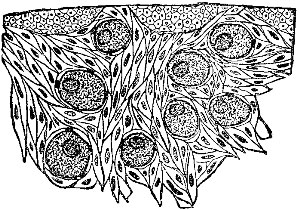

|  | |

| Fig. 8. This figure illustrates the course followed by an ovum. The ripened egg leaves the ovary (1), passes down the Fallopian tube (2), and thence into the uterine cavity (3). | Fig. 9. An exceedingly minute piece of an ovary, highly magnified. It shows eight ova or eggs. |

Object of Ovaries.—The ovaries are the essential organs of generation in the female. In each ovary are large numbers of cells, ovules, or eggs, one of which, at least, is supposed to pass into the uterine cavity with each menstruation. Anatomists tell us that each human ovary contains as many as 30,000 of these ovules, or eggs.